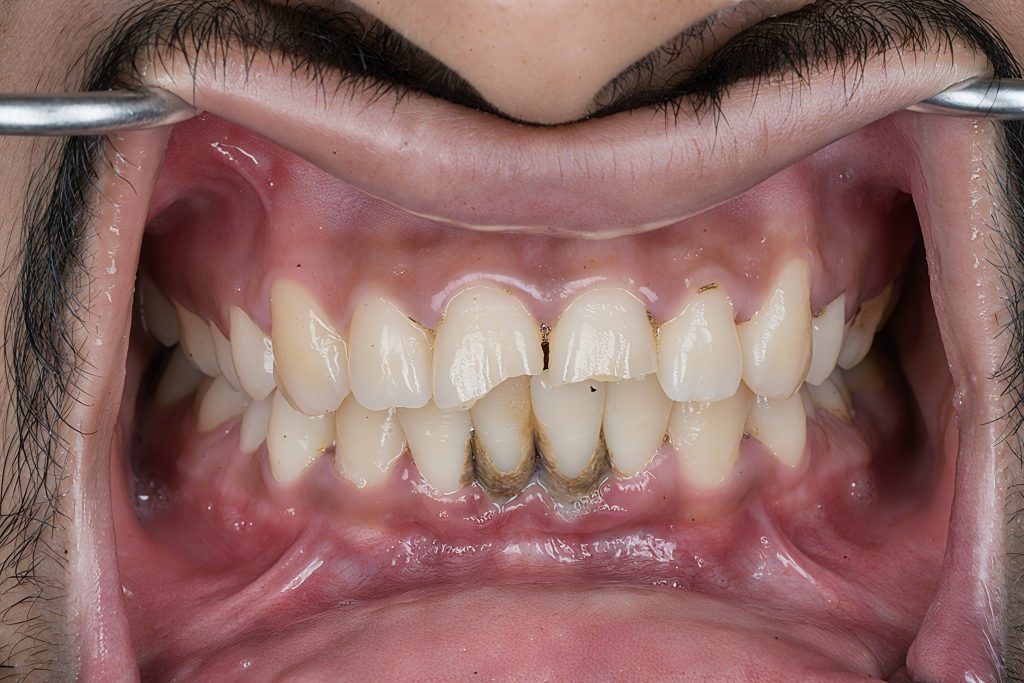

6. Shape + Texture

Macro and micro-anatomy sculpted using:

- Fine-grit burs for primary anatomy

- Blade 12 for vertical texture

- Rubber points for rounding line angles

This restored the natural youthful morphology of the incisors.

7. Polishing System

A multi-step polishing sequence was used:

- Enhance + Pogo (Dentsply) for pre-gloss

- Lucida Star + DiaShine for glass-like final gloss

- Texture maintained without over-polishing

Outcome

- Invisible transition between tooth and composite

- Natural halo effect and depth recreated

- Increased brightness without over-whitening

- Strong adhesive interface thanks to enamel bonding

- Patient extremely satisfied with the natural, clean aesthetic